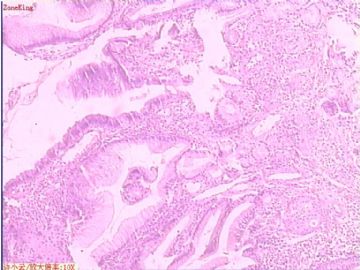

贲门息肉?

姓    名: ××× 性别:  女 年龄:  53

简要病史:  胃镜见,食道下段齿状线上可见一圆形隆起,有蒂,表面光滑,大小0.5X0.5X0.3cm.

各位老师,胃粘膜处出现的鳞状上皮有问题么?

• 贲门息肉?图4

图4

正好是齿状线腺鳞交界处粘膜

鳞状上皮没大问题,可能受炎症影响,稍有增生.

可能是炎症刺激下上皮鳞状化生

慢性炎症

本帖最后由 于 2009-11-21 09:51:00 编辑   谢谢各位老师指点,最终诊断为:贲门慢性炎症,伴局灶细胞轻度异型增生。